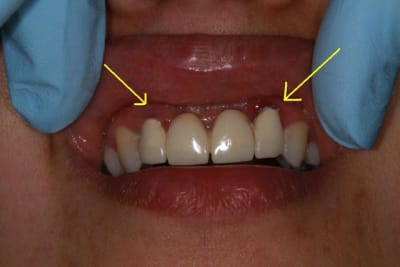

sur-traitement, pompe à fric, assassinat ...etc.. afin d'éviter tout ça je soumet à votre sagesse un cas sympa.

Patiente sympa, 30 ans, un bridge ceramo-métal fait il y a 10 ans, en fin de vie.

En réalité je sais déjà ce que je vais faire, mais implants, bridge ou pourquoi pas adjointe???

2 implants 11/21 et bridge implanto?

ne pas se servir de ces latérales qui me semblent compromises..

Bon choix mais si implants 11/21 bridge avec extensions latérales...je ne suis pas fan.

Par contre implants 12/22 et bridge ça devient raisonnable (pour moi)mais il faut enlever 12/22 et faire une pap pour les provisoires.

En général, implant 12-22 c'est plus sympa que 11-21 et des extensions.

Alors exo et implants 12-22, greffe en vestibulaire (os et muco), question de blinder le tout.

Pareil pour 11 et 21, avec greffe en vestibulaire pour garder un bon axe si nécessaire.

C'est toujours mieux de poser en 11 et 21, meilleur profil d'émergence et gestion des papilles + facile.

mon idée, après réflexion, bridge provisoire résine, pose de deux implants 11/21 et "sauvetage" de 12/22 donc 4 CCC indépendantes.

Et plus tard si 12/22 se cassent ...2 implants et toujours 4 CCC indépendantes.